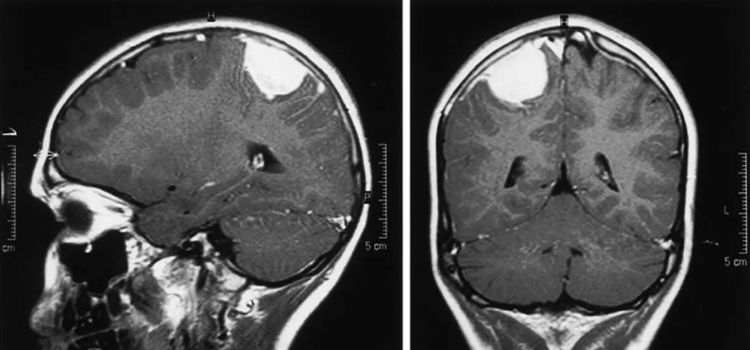

Ensayo clínico internacional para conseguir una alternativa terapéutica a pacientes con meningioma que no responden a los tratamientos 09.07.2025 El Hospital público 12 de Octubre de la Comunidad de Madrid acaba de abrir en España un ensayo clínico internacional para tratar a los pacientes de meningioma recurrente que no hayan respondido a ningún tratamiento habitual

La estimulación del sistema inmune mejora el tratamiento con virus en modelos animales del tumor cerebral infantil más agresivo 09.07.2025 Investigadores del Cima confirman que la administración intratumoral del virus Delta-24-RGD y la activación de células dendríticas abren una vía terapéutica para los pacientes con glioma difuso de línea media